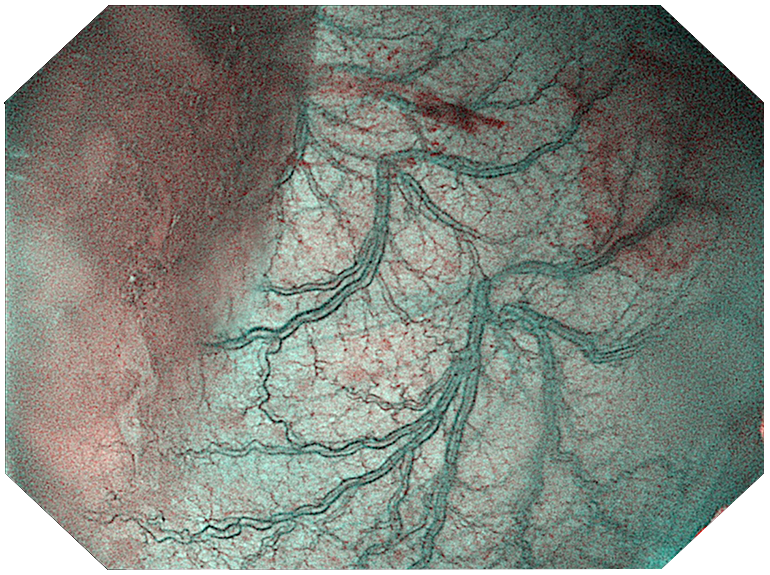

Три режима оптической хромоэндоскопии

Оснащен 4 светодиодными источниками света высокой яркости с независимым управлением, обеспечивающими многоспектральный режим окрашивания «белый свет + 3 спектра CBI». Спектральное окрашивание может повысить визуальный контраст между нормальной тканью и повреждениями, тем самым улучшая выявляемость небольших повреждений. Технология оптического окрашивания (CBI) – удобный и эффективный инструмент для выявления раннего рака, опухолевых и воспалительных процессов.

|  | CBI regular позволяет легко выявлять поражения слизистой оболочки и подчеркивать распределение подслизистых сосудов. |  |

|  | CBI indigo Усиливает контраст между слизистой оболочкой и кровеносными сосудами. |  |

|  | CBI aqua способствует лучшей визуализации структуры слизистой оболочки. |  |

Три режима оптической хромоэндоскопии (CBI). Многоспектральная визуализация с 4 светодиодами высокой яркости:

- CBI regular — визуализация слизистой и подслизистых сосудов.

- CBI indigo — усиление контраста между слизистой и сосудистой сетью.

- CBI aqua — улучшенное отображение структуры слизистой.